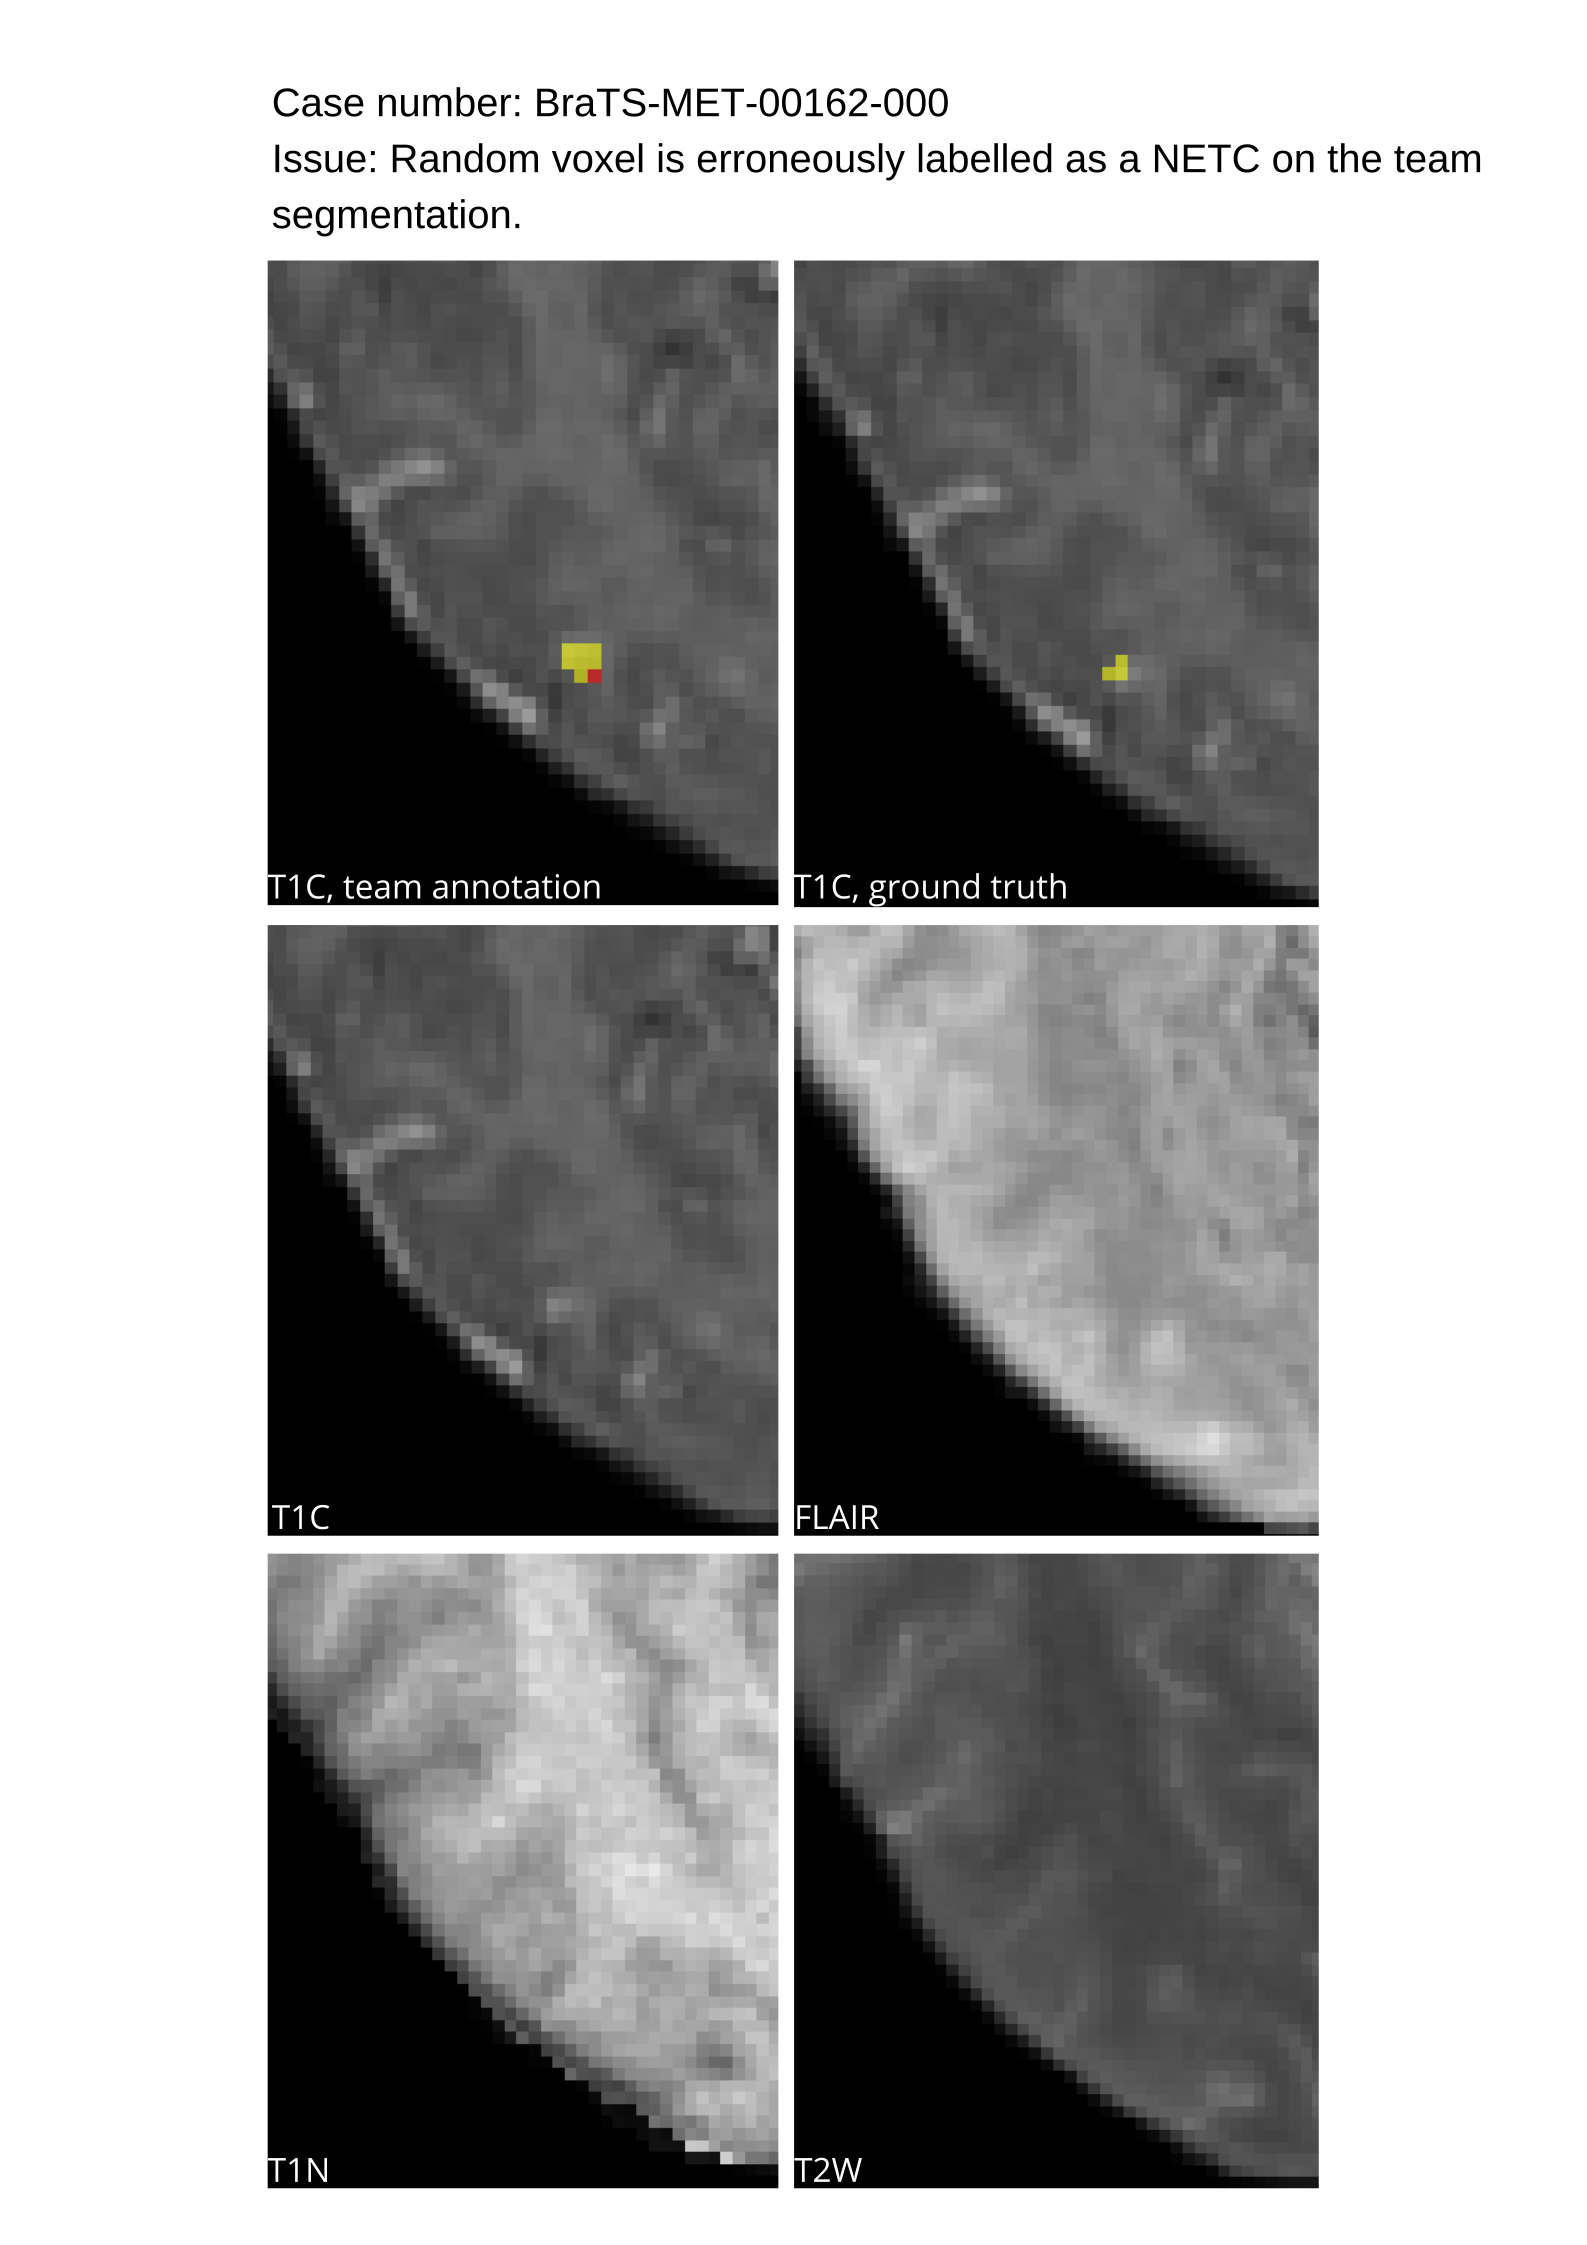

Table 4 provides the relative ranking for each team. Team NVAUTO ranked first in the challenge, with an average rank across subjects of 7.9 and a PatientWise mean of 0.38. Team SY placed second with a PatientWise mean of 0.41 across all patients. The supplementary material depicts the pitfall cases with figures illustrating the false positives or missed lesions.